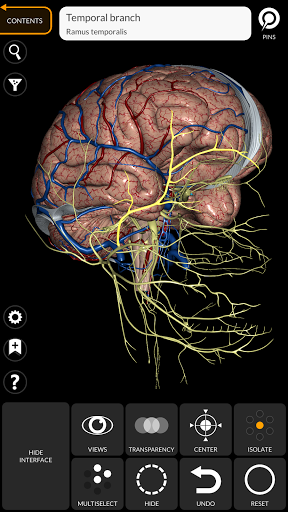

"Anatomy 3D Atlas" cho phép bạn nghiên cứu giải phẫu người theo cách dễ dàng và tương tác.

Thông qua giao diện đơn giản và trực quan, bạn có thể quan sát mọi cấu trúc giải phẫu từ mọi góc độ.

Các mô hình giải phẫu 3D đặc biệt chi tiết và có kết cấu lên đến độ phân giải 4k.

MÔ HÌNH GIẢI PHẪU 3D

• Hệ thống thần kinh

TÍNH NĂNG •

• Xoay và phóng to từng mô hình trong không gian 3D

• Tùy chọn ẩn hoặc cô lập một hoặc nhiều mô hình đã chọn

• Chức năng trong suốt

• Bằng cách chọn một mô hình hoặc một ghim, thuật ngữ giải phẫu liên quan sẽ hiển thị